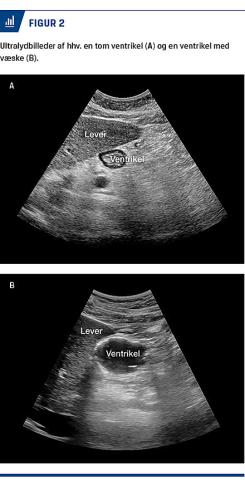

Nyere studier tyder på, at ultralydskanning kan anvendes til vurdering af, om ventriklen er tom, og at metoden kan have en rolle f.eks. hos de i Tabel 1 nævnte patienttyper. I studierne har man primært fokuseret på antrum ventriculi, da denne er let at visualisere. Der skannes med patienten lejret i henholdsvis liggende stilling og højre sideleje. Hvis antrum er tom i begge positioner, vil der være en lille risiko for aspiration

(Figur 2A). Hvis der ses fast materiale, vil aspirationsrisikoen være høj. Såfremt der er væske (Figur 2B), kan mængden estimeres vha. formler, hvor bl.a. tværsnitsarealet af ventriklen og patientens alder indgår [20]. Metoden er imidlertid behæftet med usikkerhed og er stadig under udvikling.